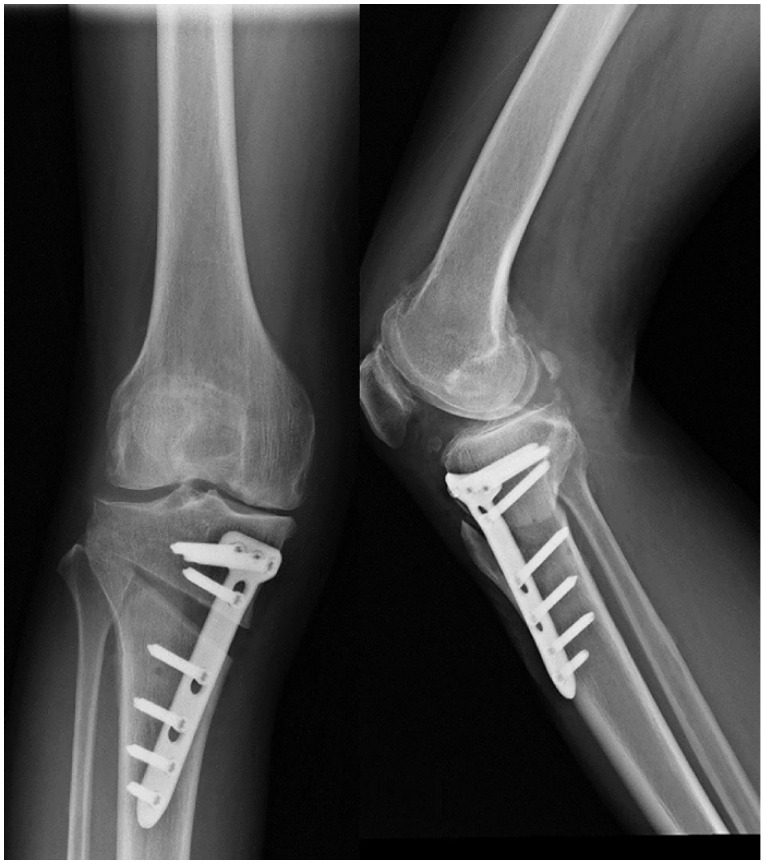

High tibial osteotomy (HTO) has been widely applied in clinical practice to treat unilateral knee osteoarthritis (OA). In order to improve the effectiveness of surgical treatment, researchers attempted to use a combination of platelet-rich plasma (PRP) and HTO therapy. We summarized the clinical outcomes of engaging HTO and PRP and found promising clinical advantages in improving postoperative pain and function, promoting cartilage repair, and increasing bone cartilage structure in patients. Further studies are needed to provide more convincing evidence of the efficacy of the combined therapy.